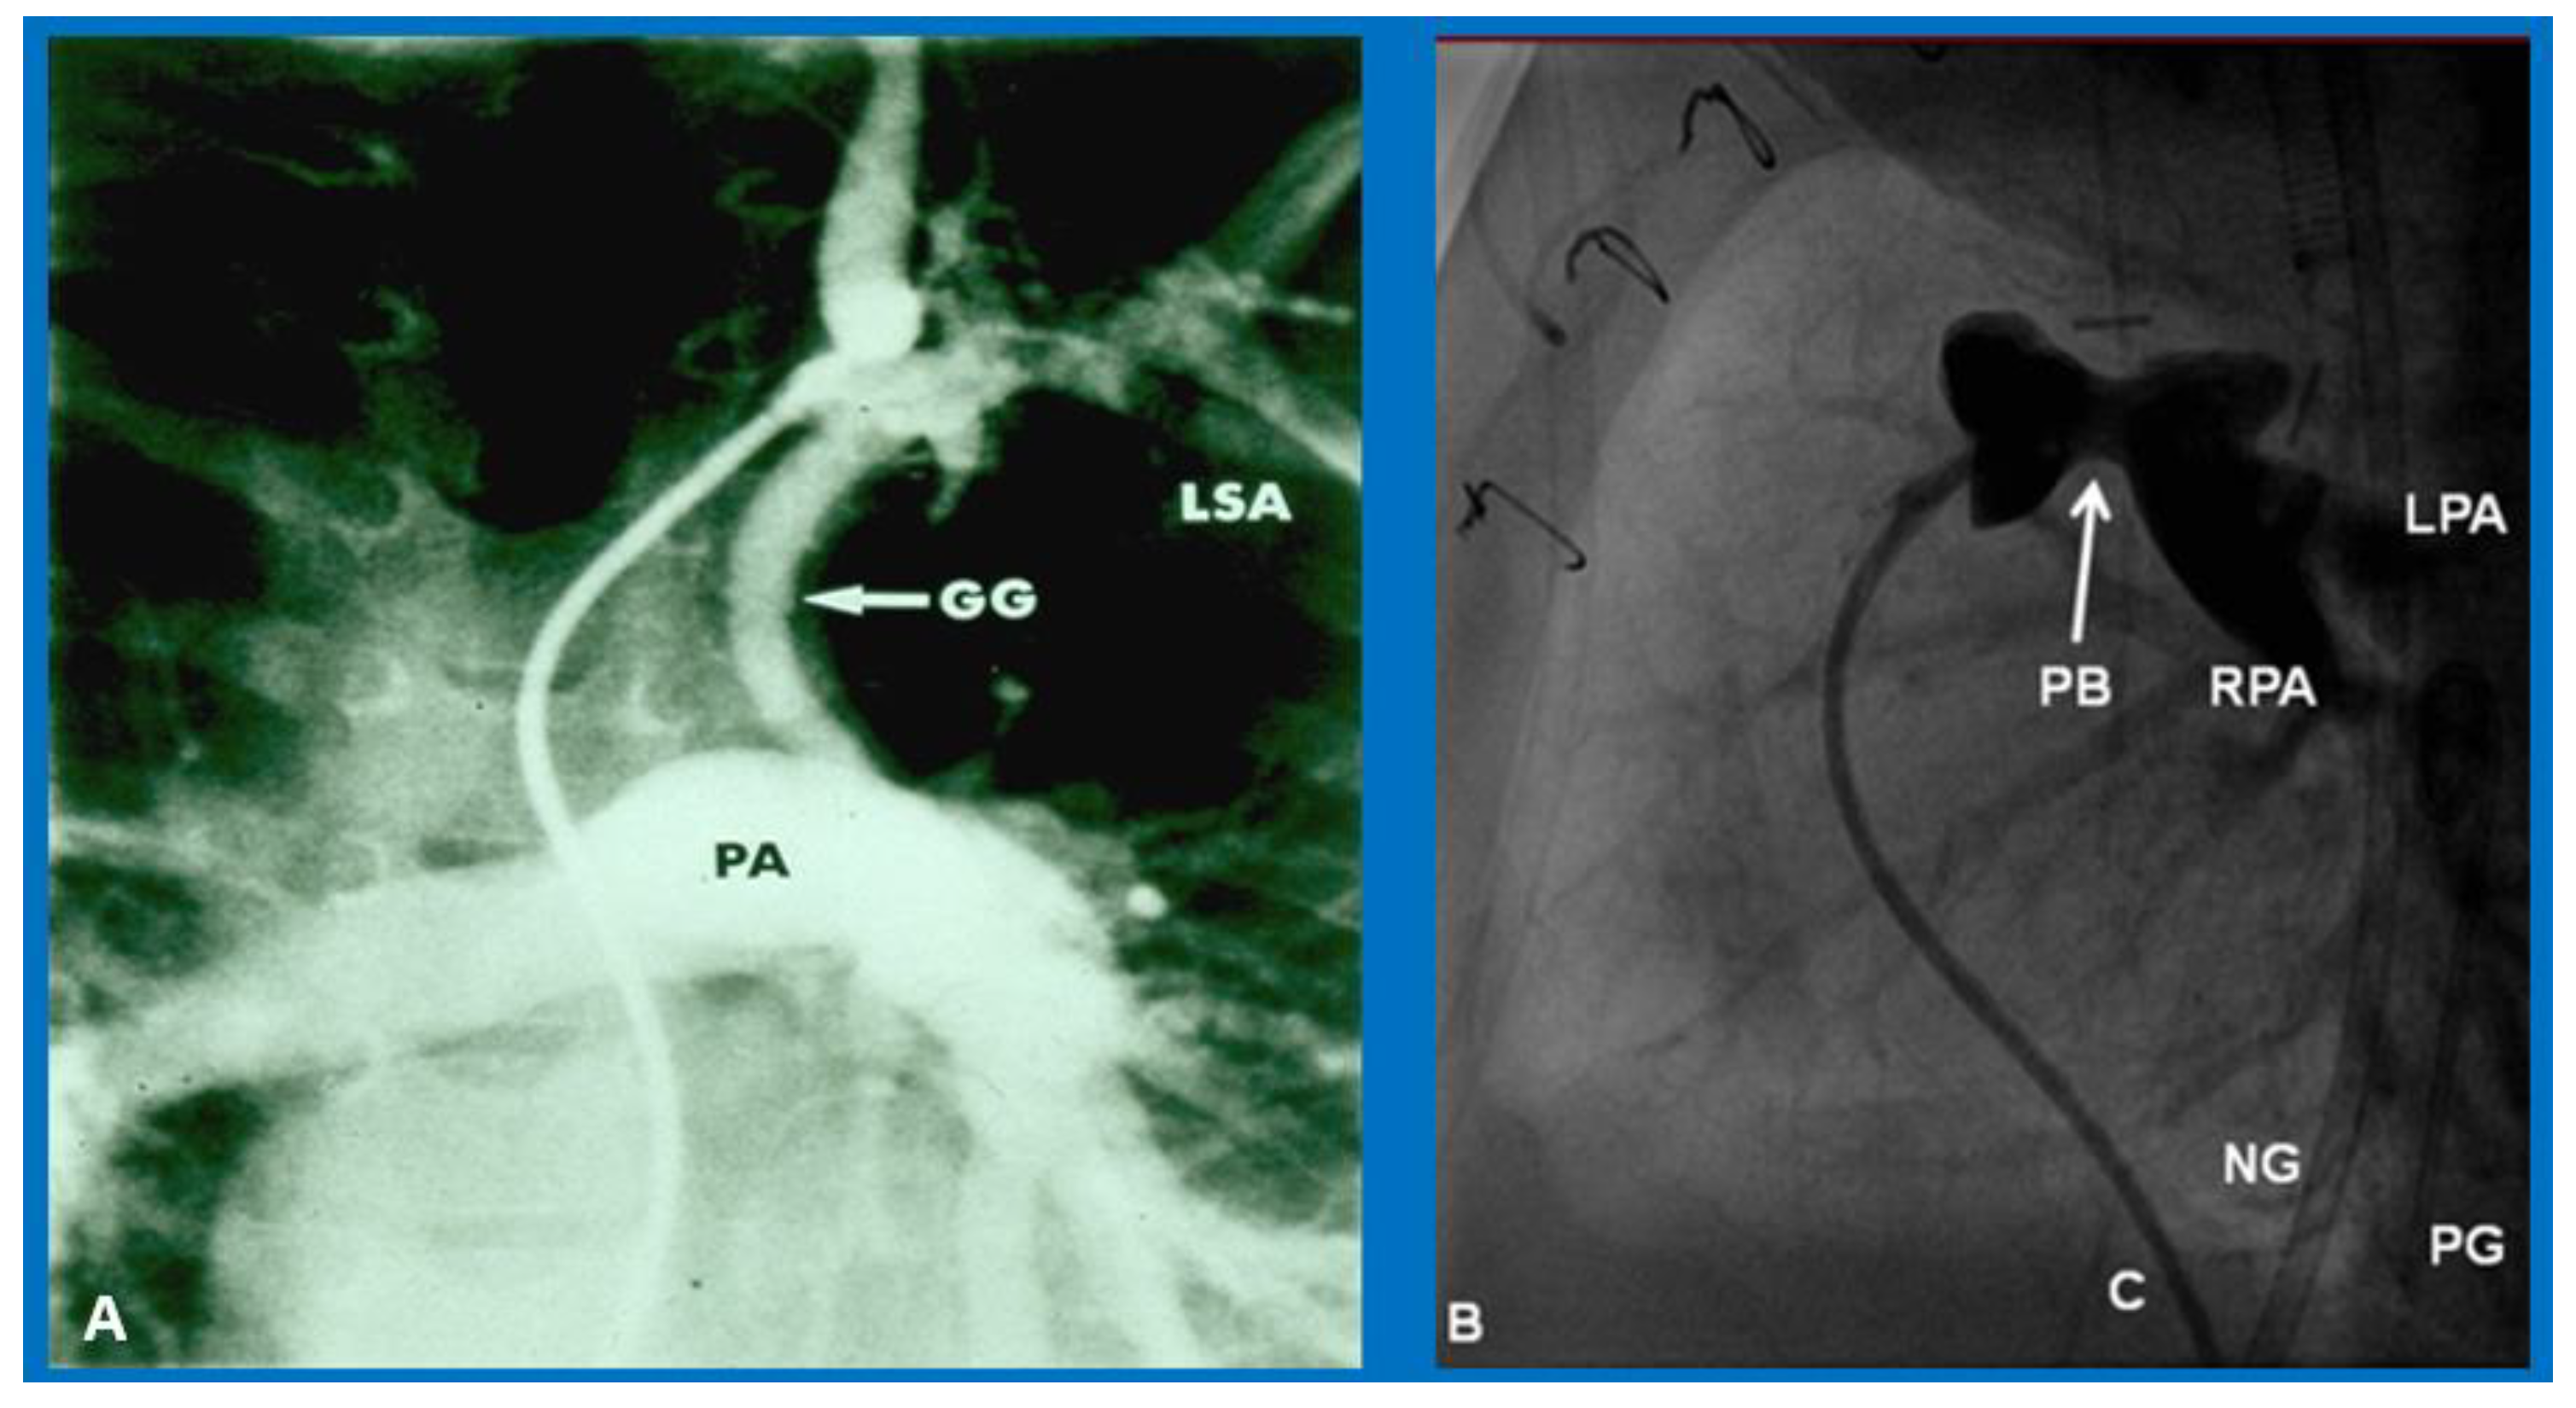

5. Physical Examination

9. Cardiac Catheterization with Angiography, Magnetic Resonance Imaging (MRI) and Computed Tomography (CT)